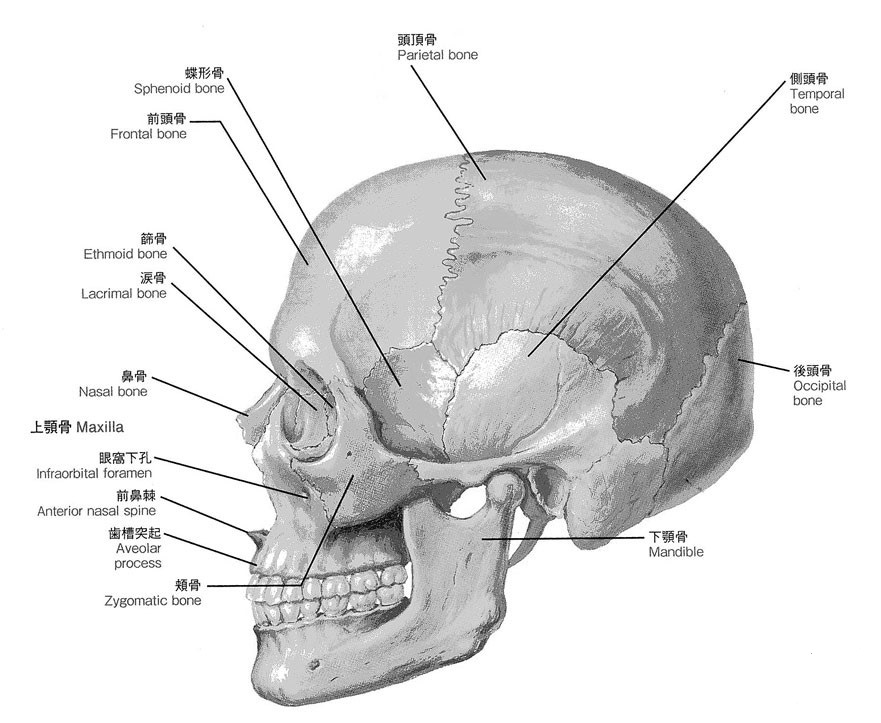

1:上顎骨とは

上顎骨は、顔面の中心において大部分をなし、左右対称に1対存在し、正中で縫合している骨の事です。

上顎骨は下顎骨を除いた顔面頭蓋骨の中で最も大きく、上顎の大部分を占めています。

上顎骨には上顎の歯牙が植わっており、左右の頬骨と繋がり、硬口蓋前部と鼻腔側壁および鼻腔底、眼窩底を形づくります。

上顎骨を構成するものは上顎骨体(上顎体)とそれに付随する前頭突起、頬骨突起、口蓋突起、歯槽突起の4つの骨突起です。